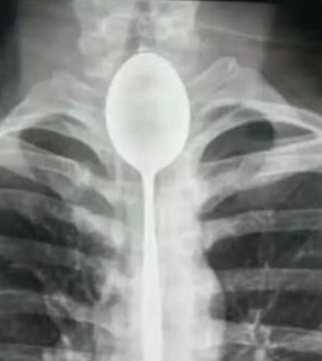

Chinese Doctors Remove a Spoon out of a Mans Throat

Chinese doctors remove spoon from man’s throat!

Chinese doctors have removed a 20-centimetre long spoon which was stuck in a man’s throat for a year.

The man, named as Mr Zhang, swallowed the spoon in 2017. However, he suffered no pain or discomfort and did not seek medical attention to remove the utensil.

It wasn’t until he was recently hit in the chest that the spoon became a problem.

It took two hours to retrieve the spoon, with the procedure carrying a risk of perforating his oesophagus.

Mr Zhang recovered well from the procedure and was discharged two days later.